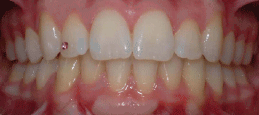

Class II Div II |